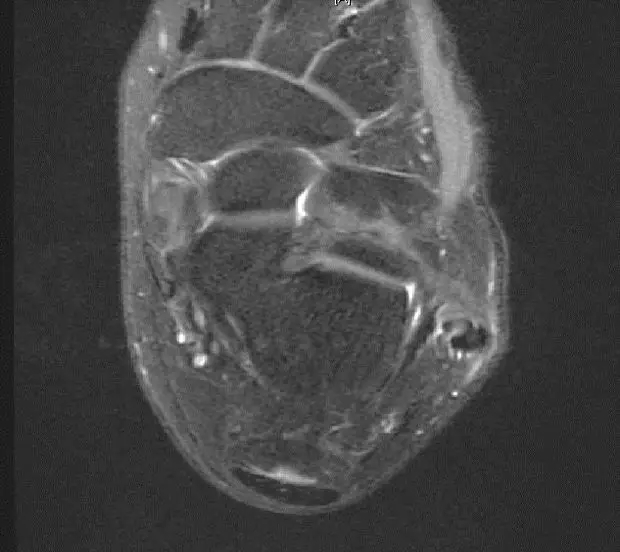

从这张片子我们可以看到正常的韧带结构,包括距腓前韧带,跟绯韧带,它是质地比较均一,T2相高信号,连续性良好,并且有良好的张力,从冠状位也可以看到跟绯韧带,在腓骨肌腱的深方,也是T2相跟T1相的低信号,有良好的连续性,张力也不错。